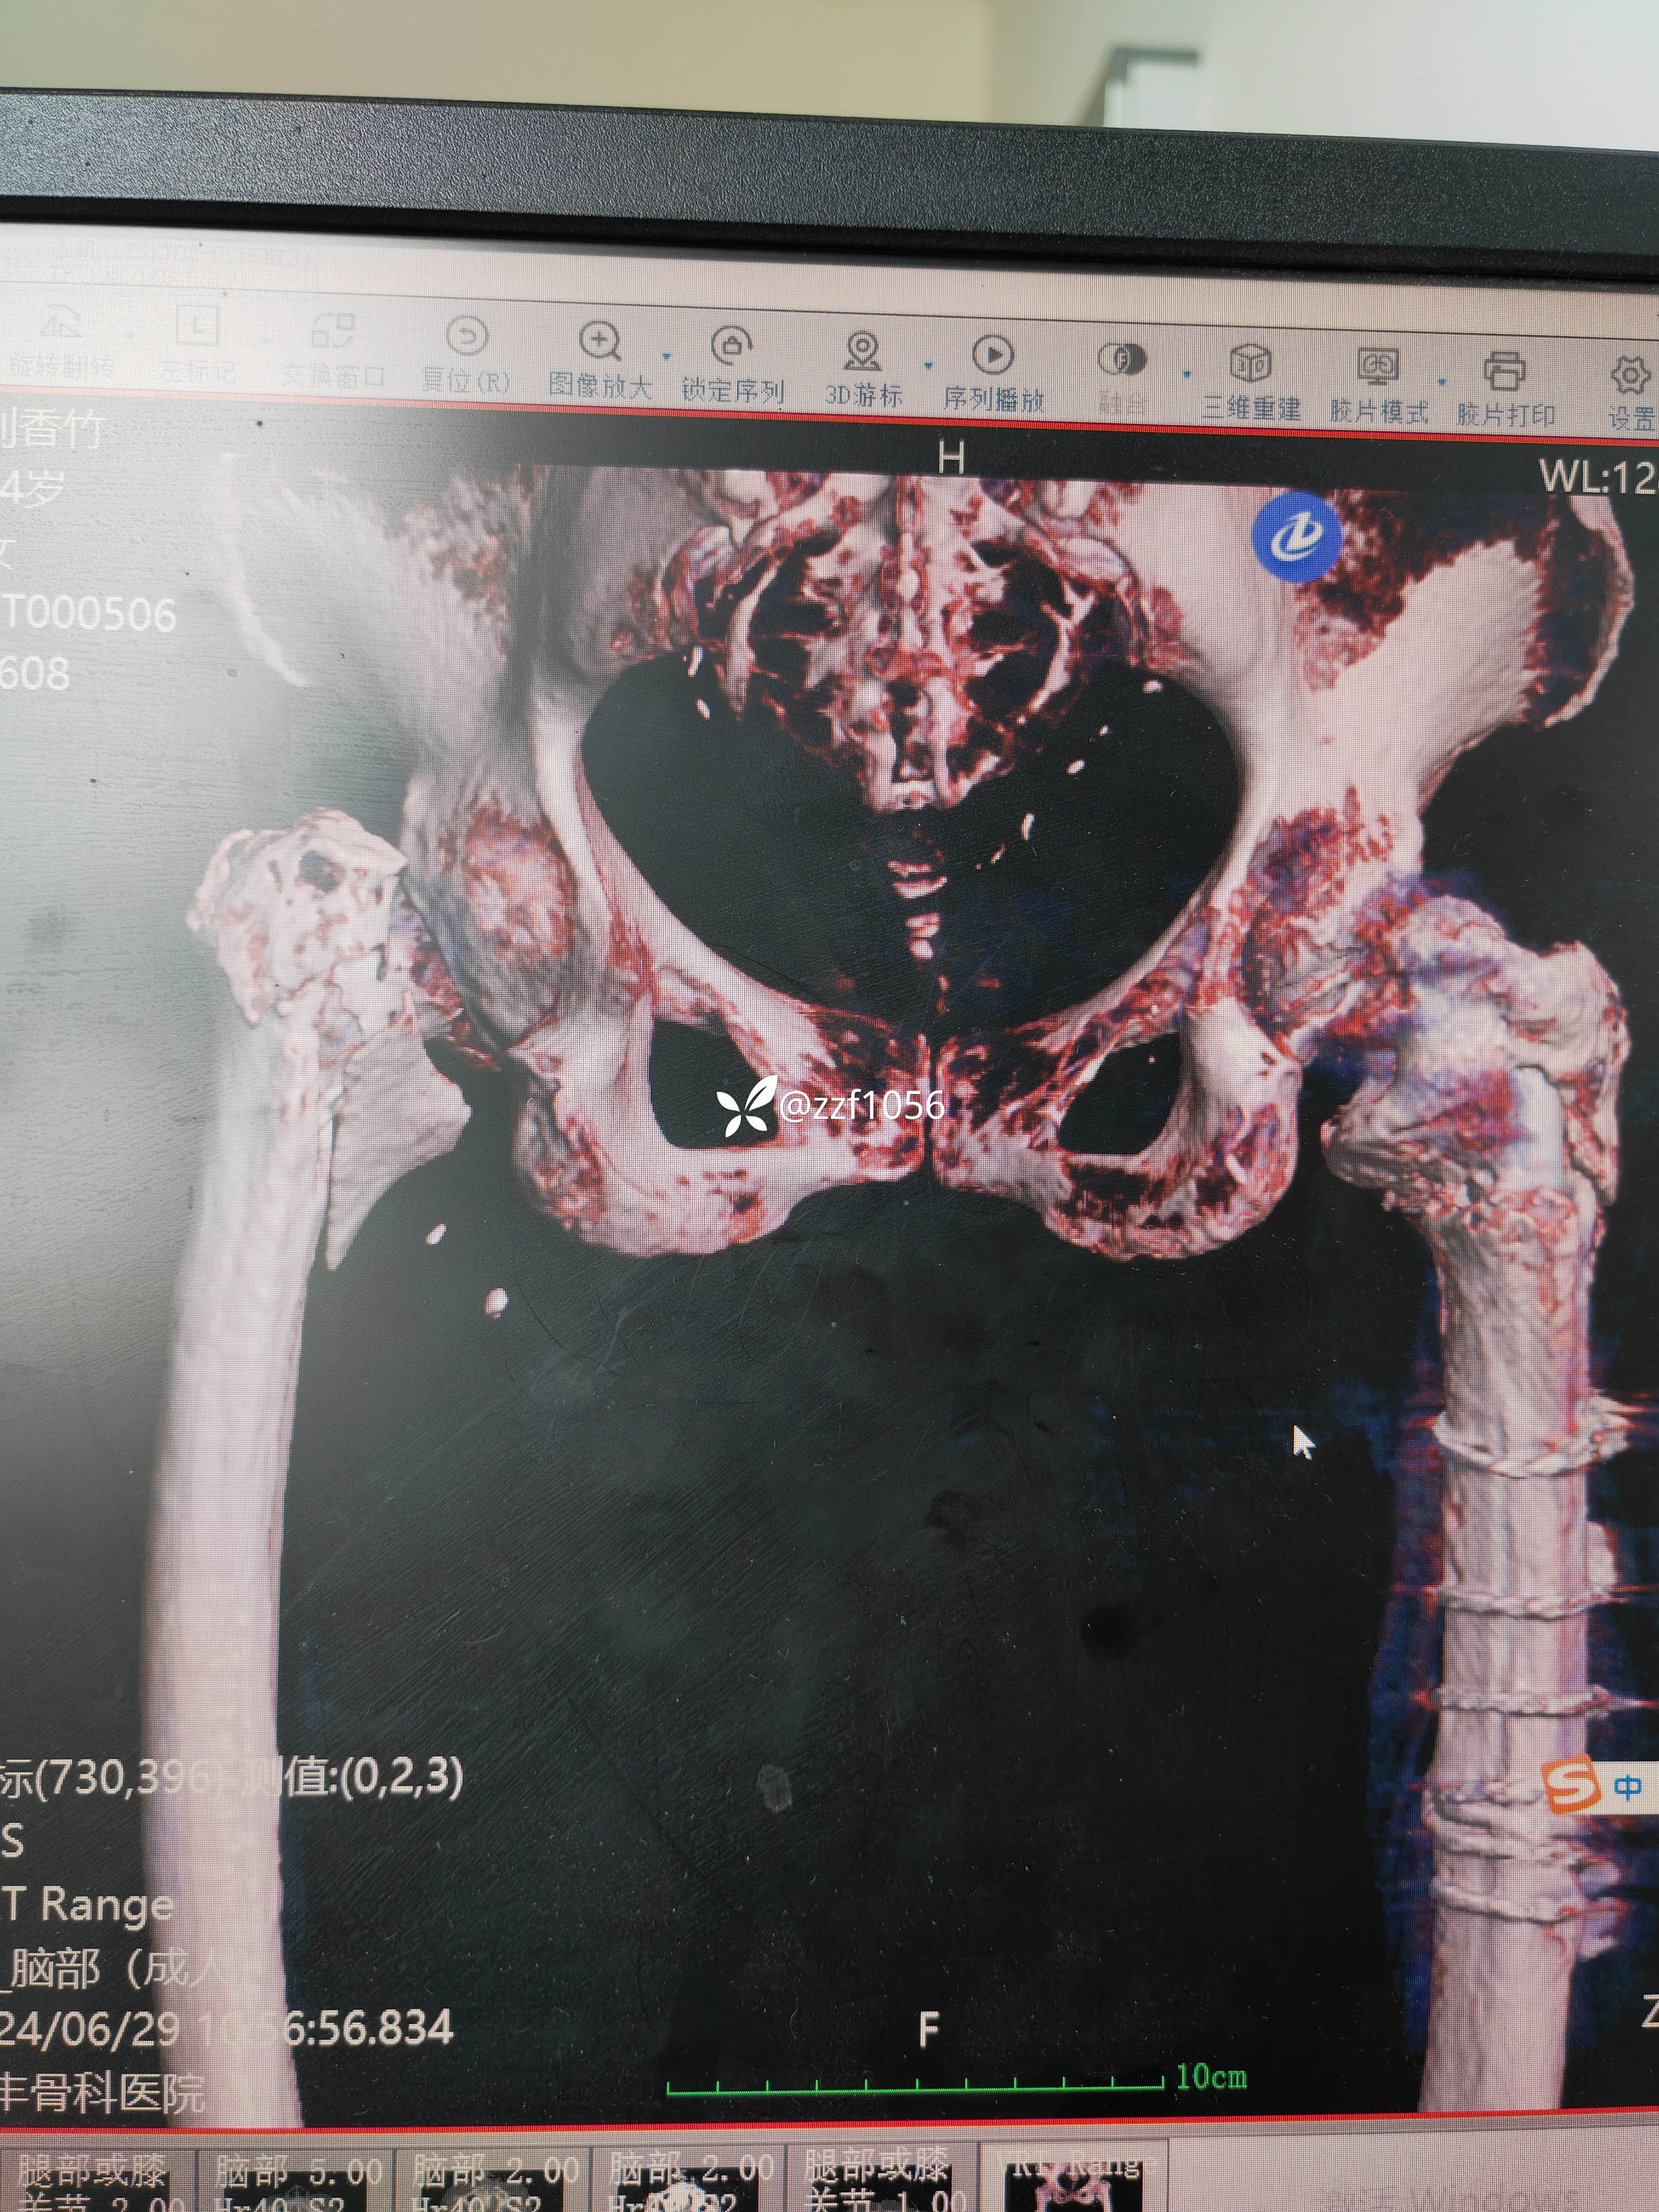

行走三个月康复良好,奈何再次摔伤,导致左侧转子间再骨折,A2.3型